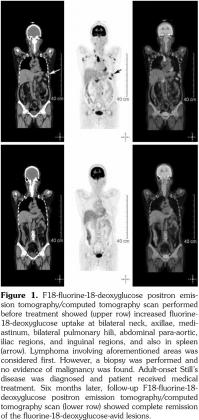

In this case, we were unable to diagnose bone marrow involvement since no bone marrow biopsy was performed. There was mild and diffuse increase of FDG uptake in the bone marrow with a maximum standard uptake value of 2.5 in the spines, which was similar to the FDG uptake in the liver. According to a study by Inoue et al.,(14) a bone marrow F-18 FDG uptake greater than or equal to that of the liver may indicate bone marrow hyperactivity. Therefore, bone marrow involvement could not be ruled out in this case. The PET/CT six months later revealed that the maximum standard uptake value decreased to 2.0 in the spines and was less than that in the liver (Figure 3).